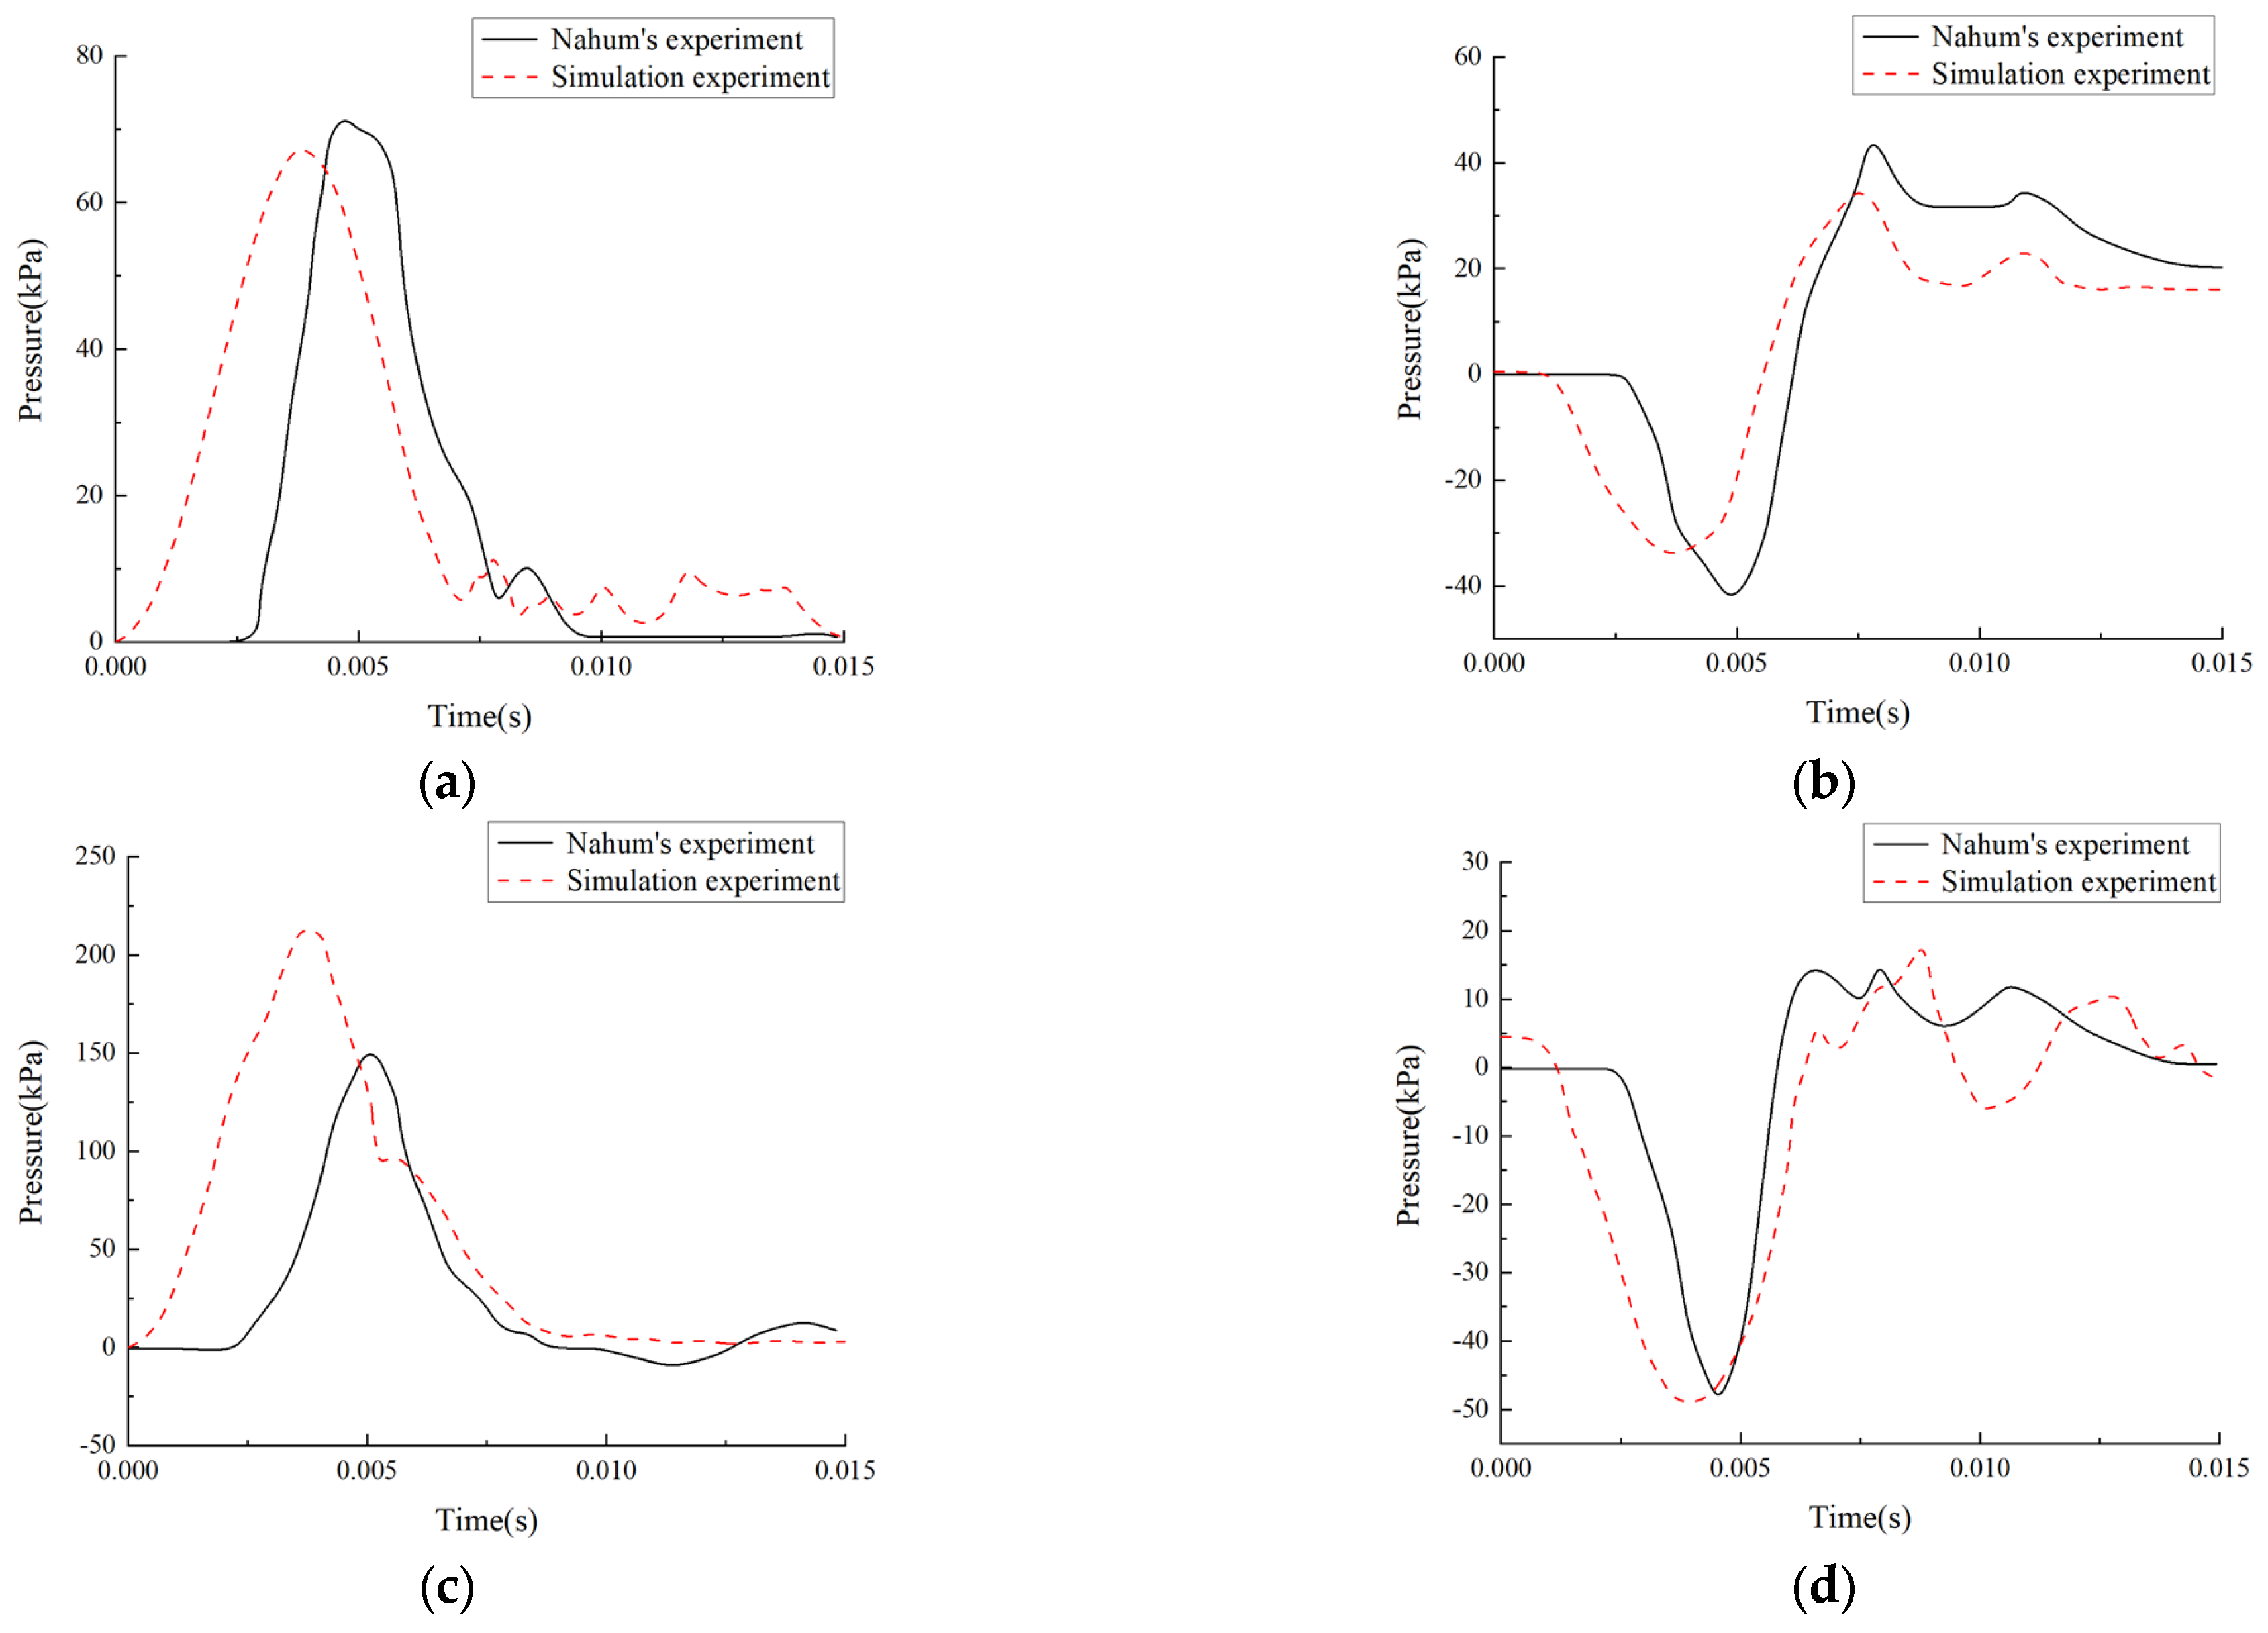

2.1.2. Experimental Validation of Nahum’s Intracranial Pressure